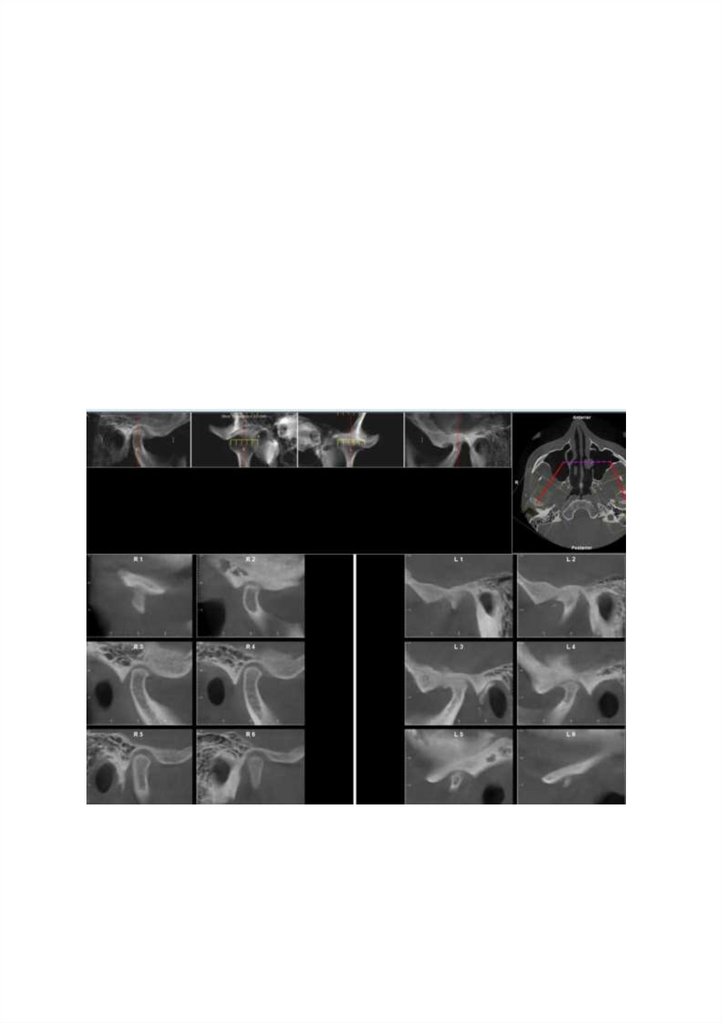

V*

Заключение

КТ-картима дегенеративно-дистрофических изменения височно-нижнечелюстных суставов с преобладаниями

изменений слева Свободный костный фрагмент в полости левого височно-нижнечелюстного сустава

Рекомендовано:

V

Врач

/ Сидоренко Алексей Сергеевич

Дата 16 04 2025